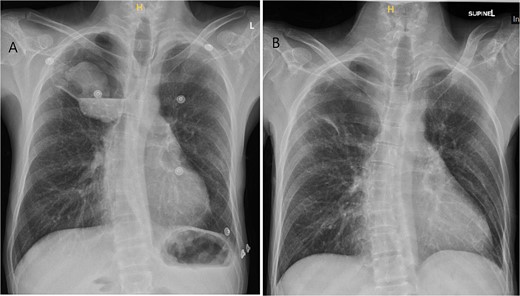

A 36-year-old male was referred to the Thoracic Surgery Service due to an incidental finding of a 5-cm soft tissue density within a known long-standing large right apical bulla on a chest X-ray (Fig. 1A). This lesion was new compared to the patient’s last chest X-ray 5 months prior (Fig. 1B). A computed tomography (CT) scan of the chest, abdomen, and pelvis demonstrated a 4.4 × 5.2 cm intracavitary solid-appearing mass within the wall of the longstanding bulla, along with heterogeneous fluid layering within the cavity with questionable enhancement (Fig. 2). This was reported as concerning for a primary bronchogenic malignancy (versus adherent fungus ball) with a superimposed infection. The patient had no respiratory or constitutional symptoms.

CT imaging of right intracavitary lung mass found within the wall of a longstanding bulla, along with heterogeneous fluid layering within the cavity (A). The mass was reported to be 4.4 × 5.2 cm and was concerning for primary bronchogenic malignancy. This lesion increased to 6.8 × 5.9 cm, demonstrating intense increased FDG activity and interval increase in fluid layering within the bulla within 2 months on follow-up PET imaging (B).

A PET scan done 2 months after the original CT scan showed that the lesion had increased in size (3.3 × 6.8 × 5.9 cm compared to previous CT findings of 2.7 × 3.9 cm), and demonstrated intense increased fludeoxyglucose (FDG) activity, with several smaller foci of similar intense grade FDG avid soft tissue nodules along the posterior aspect of the inferior bulla (Fig. 2). There was also an interval increase in fluid layering within the bulla. There was no distant metastasis.